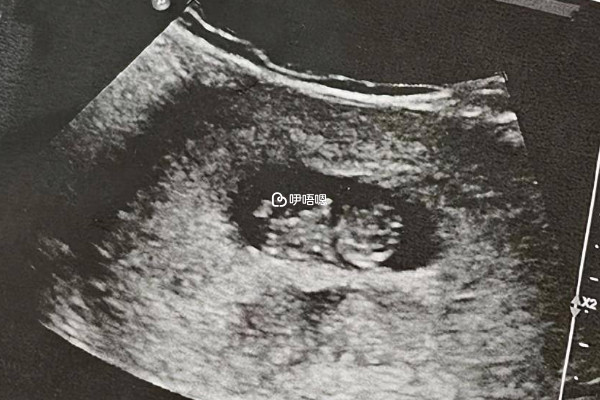

結合上文來看,封閉抗體陰性會增加懷孕早期終止懷孕的風險,所以此類孕婦在胎停高發期更要謹慎小心。一般懷孕10周時,是胎兒停產的高發期,即懷孕早期,應注意每隔三到五天覆查HCG和孕酮。日常生活中不要勞累,孕婦需要多吃營養豐富的食物,定期做好產前檢查,調節情緒,不要進行性生活。